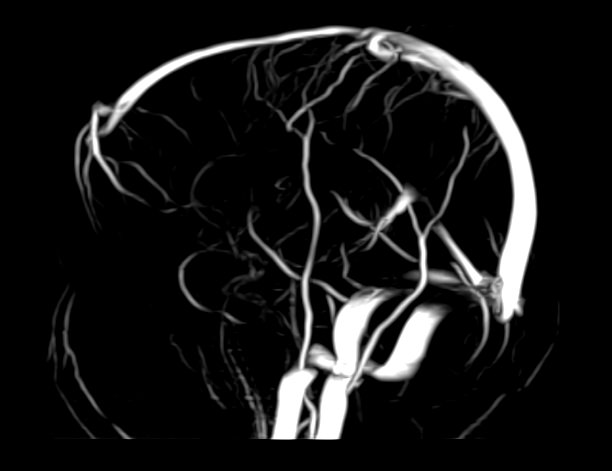

Магнитно-резонансная ангиография артериальной и венозной систем головного мозга позволяет получить трехмерное изображение сосудистой системы, кровоснабжающей центральную нервную систему, оценить анатомическое строение артерий и вен головного мозга и функциональные особенности кровотока.

С помощью внешнего магнитного поля томограф послойно сканирует структуры головного мозга, затем посредством компьютерных программ преобразует полученные данные в трехмерное изображение. При этом на снимке видна только сосудистая система без окружающих тканей. Таким образом, сканирование в режиме ангиографии позволяет визуализировать артерии и вены головного мозга без контрастирования.